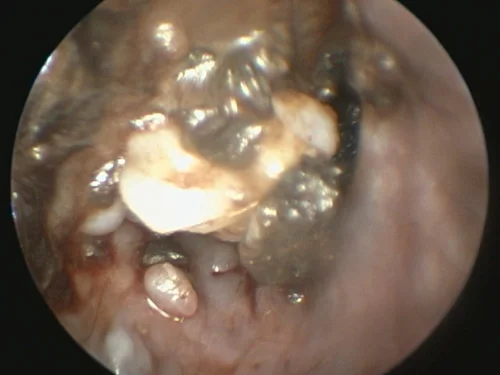

Ear disease often recurs and persists in dogs due to incomplete or ineffective treatments or failure to diagnose the underlying cause. To improve the treatment of pets with chronic ear disease, our experienced veterinarians often utilize video otoscopy.

Video otoscopy has revolutionized the treatment of ear infections by our medical team as it provides amazing clarity to assess the condition of the ear canal, eardrum, and, at times, the middle ear.

Video otoscopy is the use of a small rigid otoscope with a camera built in that can be passed into the ear canal. The image is then projected onto a screen allowing magnification and much greater clarity to observe the deeper ear canal and structures.

Small channels within the otoscope also allow instruments to be passed into the ear canal to facilitate deeper cleaning, polyp or tumor removal, and other procedures. The use of video otoscopy in a challenging ear case is often the difference between months of continued struggles and a much more rapid resolution of infection and disease.